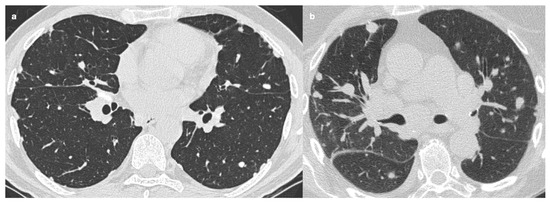

CT Imaging Features of Pulmonary Sarcoidosis: Typical and Atypical Radiological Features and Their Differential Diagnosis

Sarcoidosis is a chronic, idiopathic, multisystemic inflammatory disease characterized by non-caseating granulomas, most commonly affecting the lungs and mediastinal lymph nodes. Radiological imaging plays a fundamental role in the diagnosis, assessment of disease extent, and differentiation from other pulmonary conditions. This narrative review offers a comprehensive overview of the imaging features of pulmonary sarcoidosis, focusing on both typical patterns—such as bilateral hilar lymphadenopathy, perilymphatic nodules, and upper lobe-predominant infiltrates—and atypical manifestations—including alveolar opacities, miliary nodules, fibrocystic changes, and lower lobe involvement. Emphasis is placed on the utility of high-resolution computed tomography (HRCT) in detecting early parenchymal changes and complications such as fibrosis, bronchiectasis, and pulmonary hypertension. Differential diagnosis, including tuberculosis, silicosis, metastatic disease, organizing pneumonia, and hypersensitivity pneumonitis, are discussed to aid interpretation. Recognizing the spectrum of radiological presentations is essential for distinguishing sarcoidosis from other interstitial and granulomatous lung diseases. Radiologists play a pivotal role in the multidisciplinary diagnostic process, contributing to timely diagnosis, risk stratification, and optimized patient management. Full article

Figure 1